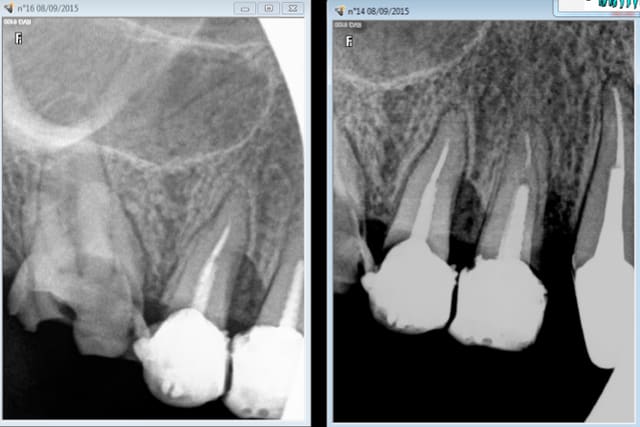

Comment cotez vous ces clichés ?

HBQK191 (16, 14)

Dents contiguës de 16 : 17,15

Dents contigues de 14 : 15, 13

2 secteurs distincts ? ou pas assez centré sur 16 ( qui est tout aussi centrée que 15) ? -)))))